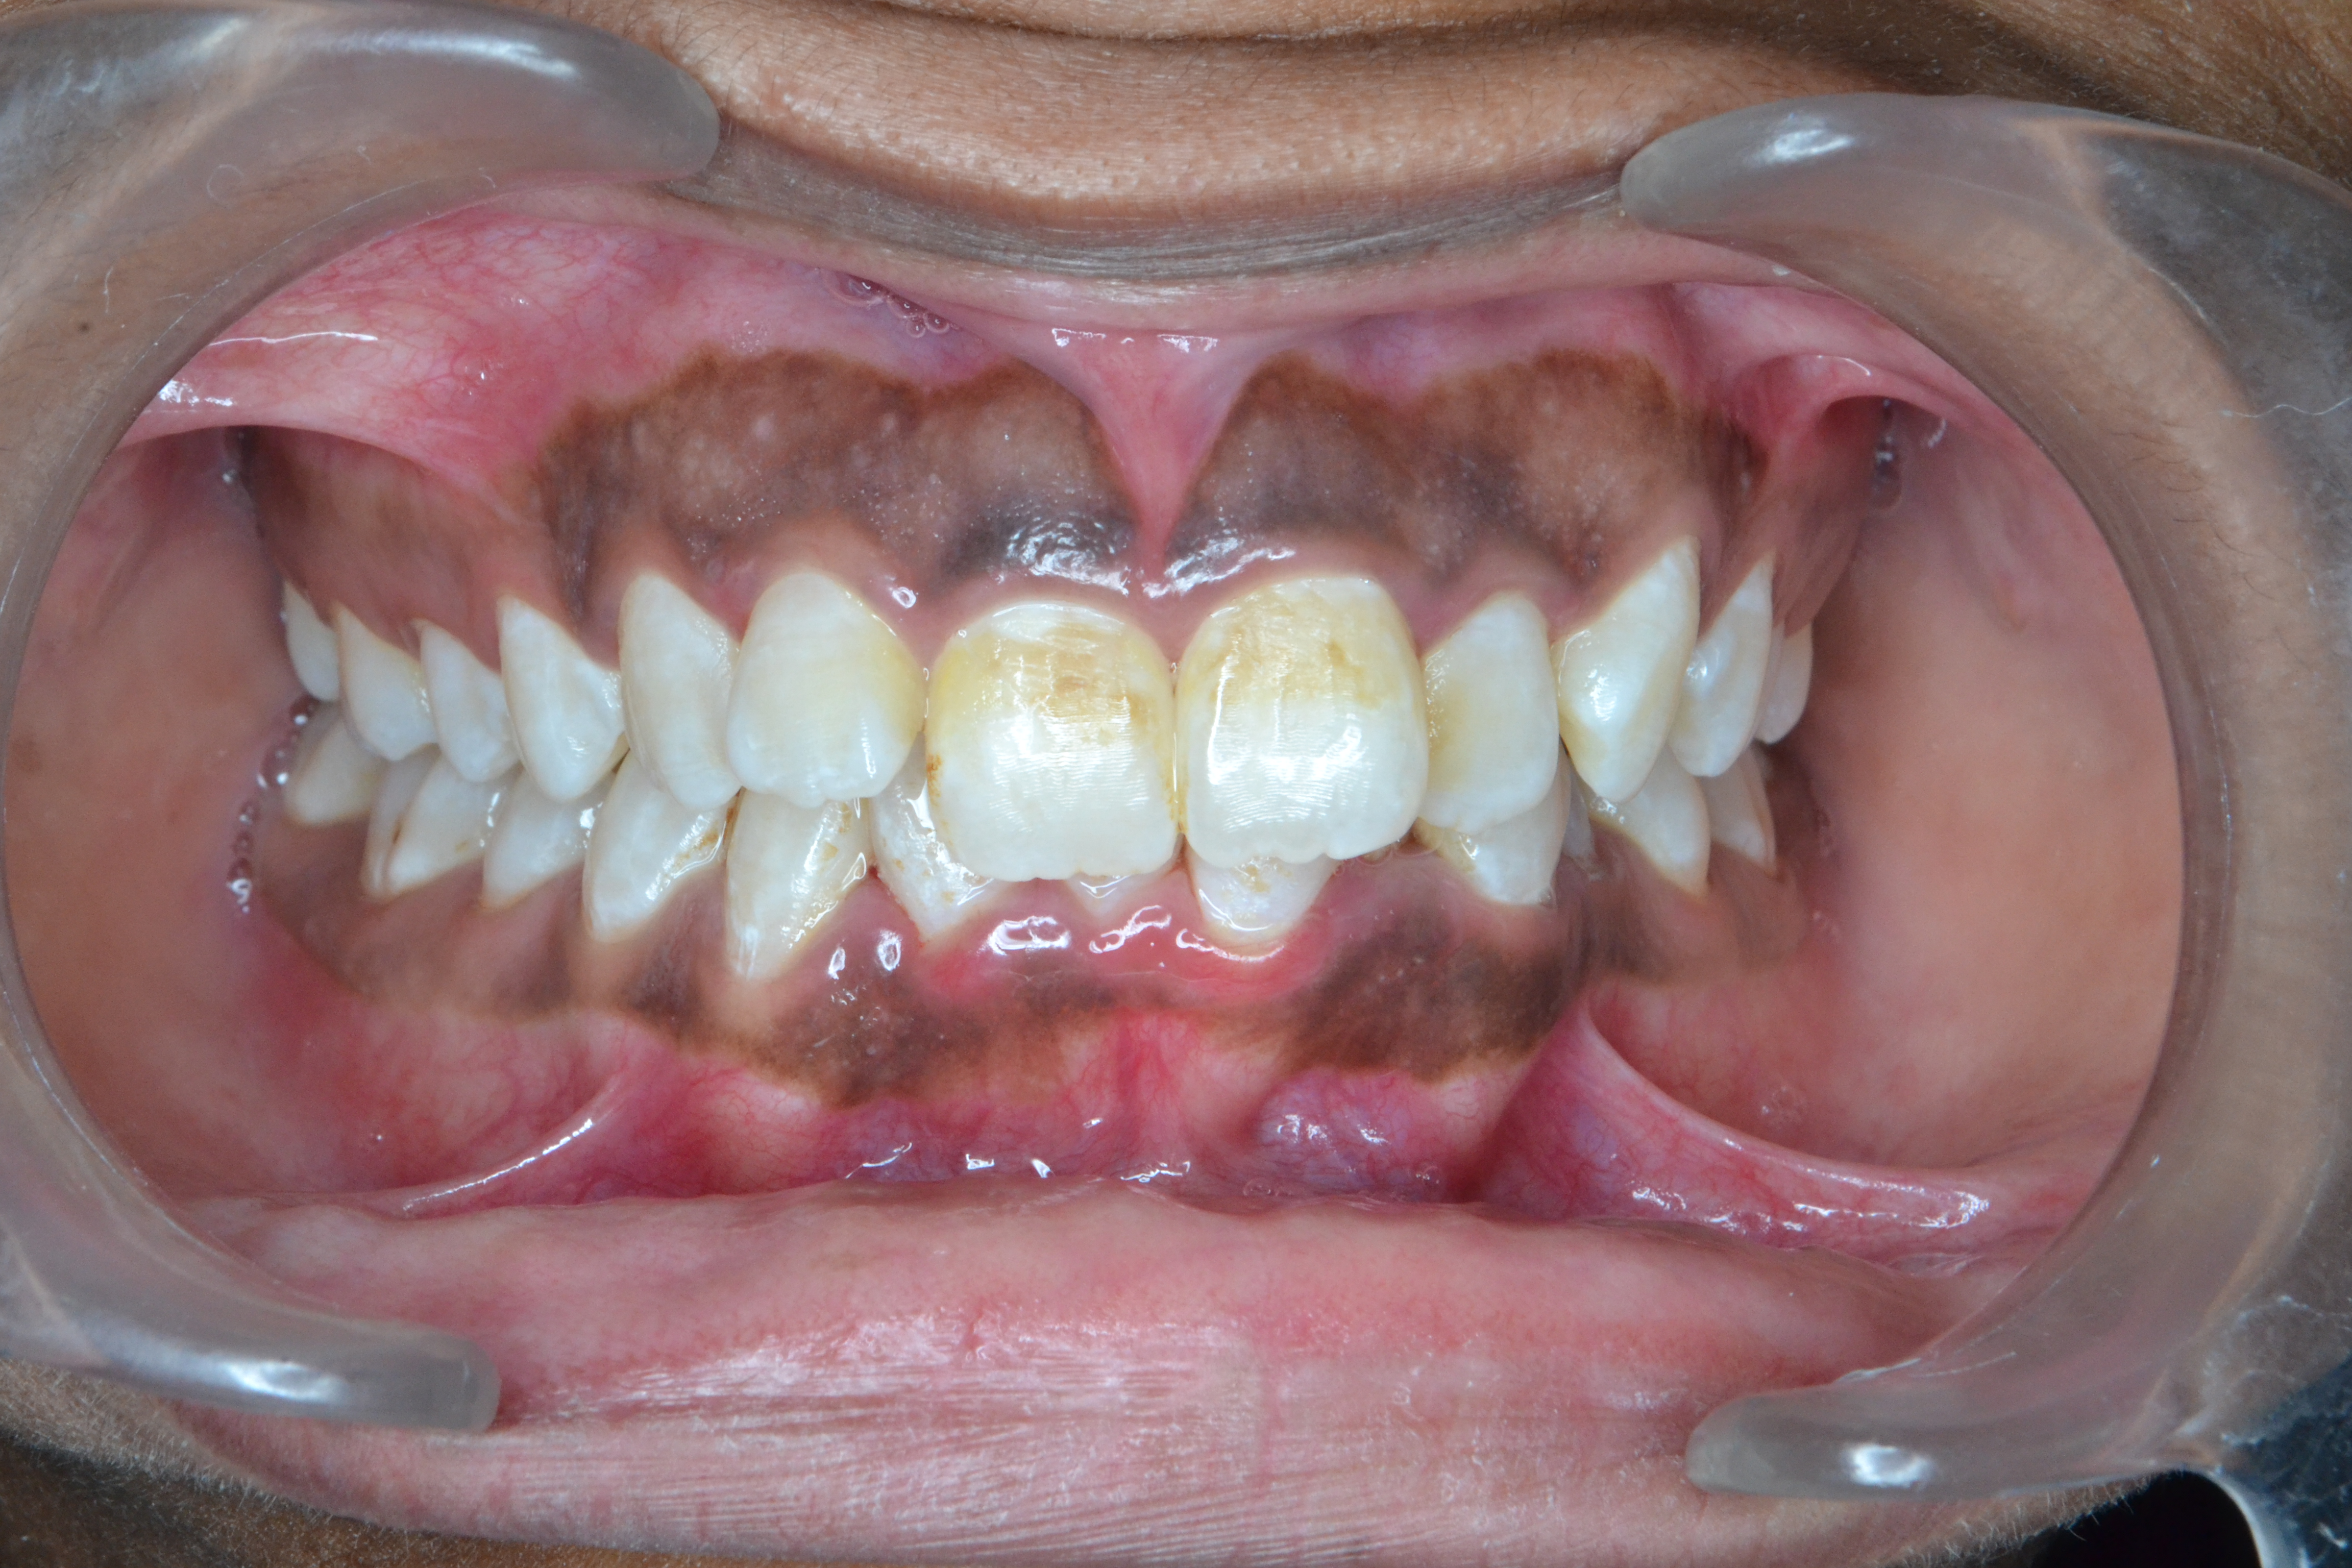

After/Before

See stunning smile transformation before and after

Before After